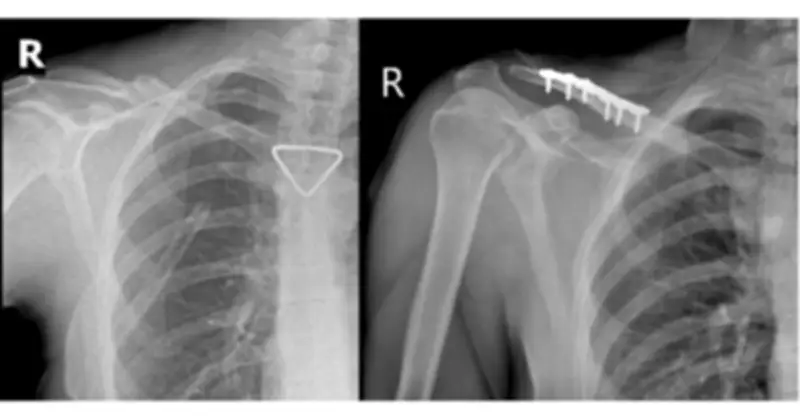

Kết quả chẩn đoán cho thấy bệnh nhân bị tràn khí màng phổi phải lượng nhiều, gây chèn ép phổi nghiêm trọng. Ngoài ra, anh còn bị gãy cung bên xương sườn thứ 2, 3, 4 bên phải và gãy phức tạp một phần ba giữa xương đòn phải với di lệch nhiều kèm mảnh rời. Tình trạng này đe dọa trực tiếp đến tính mạng do nguy cơ suy hô hấp nặng.

Ca mổ do ê-kíp Bác sĩ chuyên khoa II Trần Văn Dương và Bác sĩ Phạm Ngọc Huy thực hiện, diễn ra thuận lợi. Nẹp vít được đặt vững chắc, trục xương phục hồi giải phẫu tốt, như minh chứng qua hình ảnh X-quang trước và sau mổ.